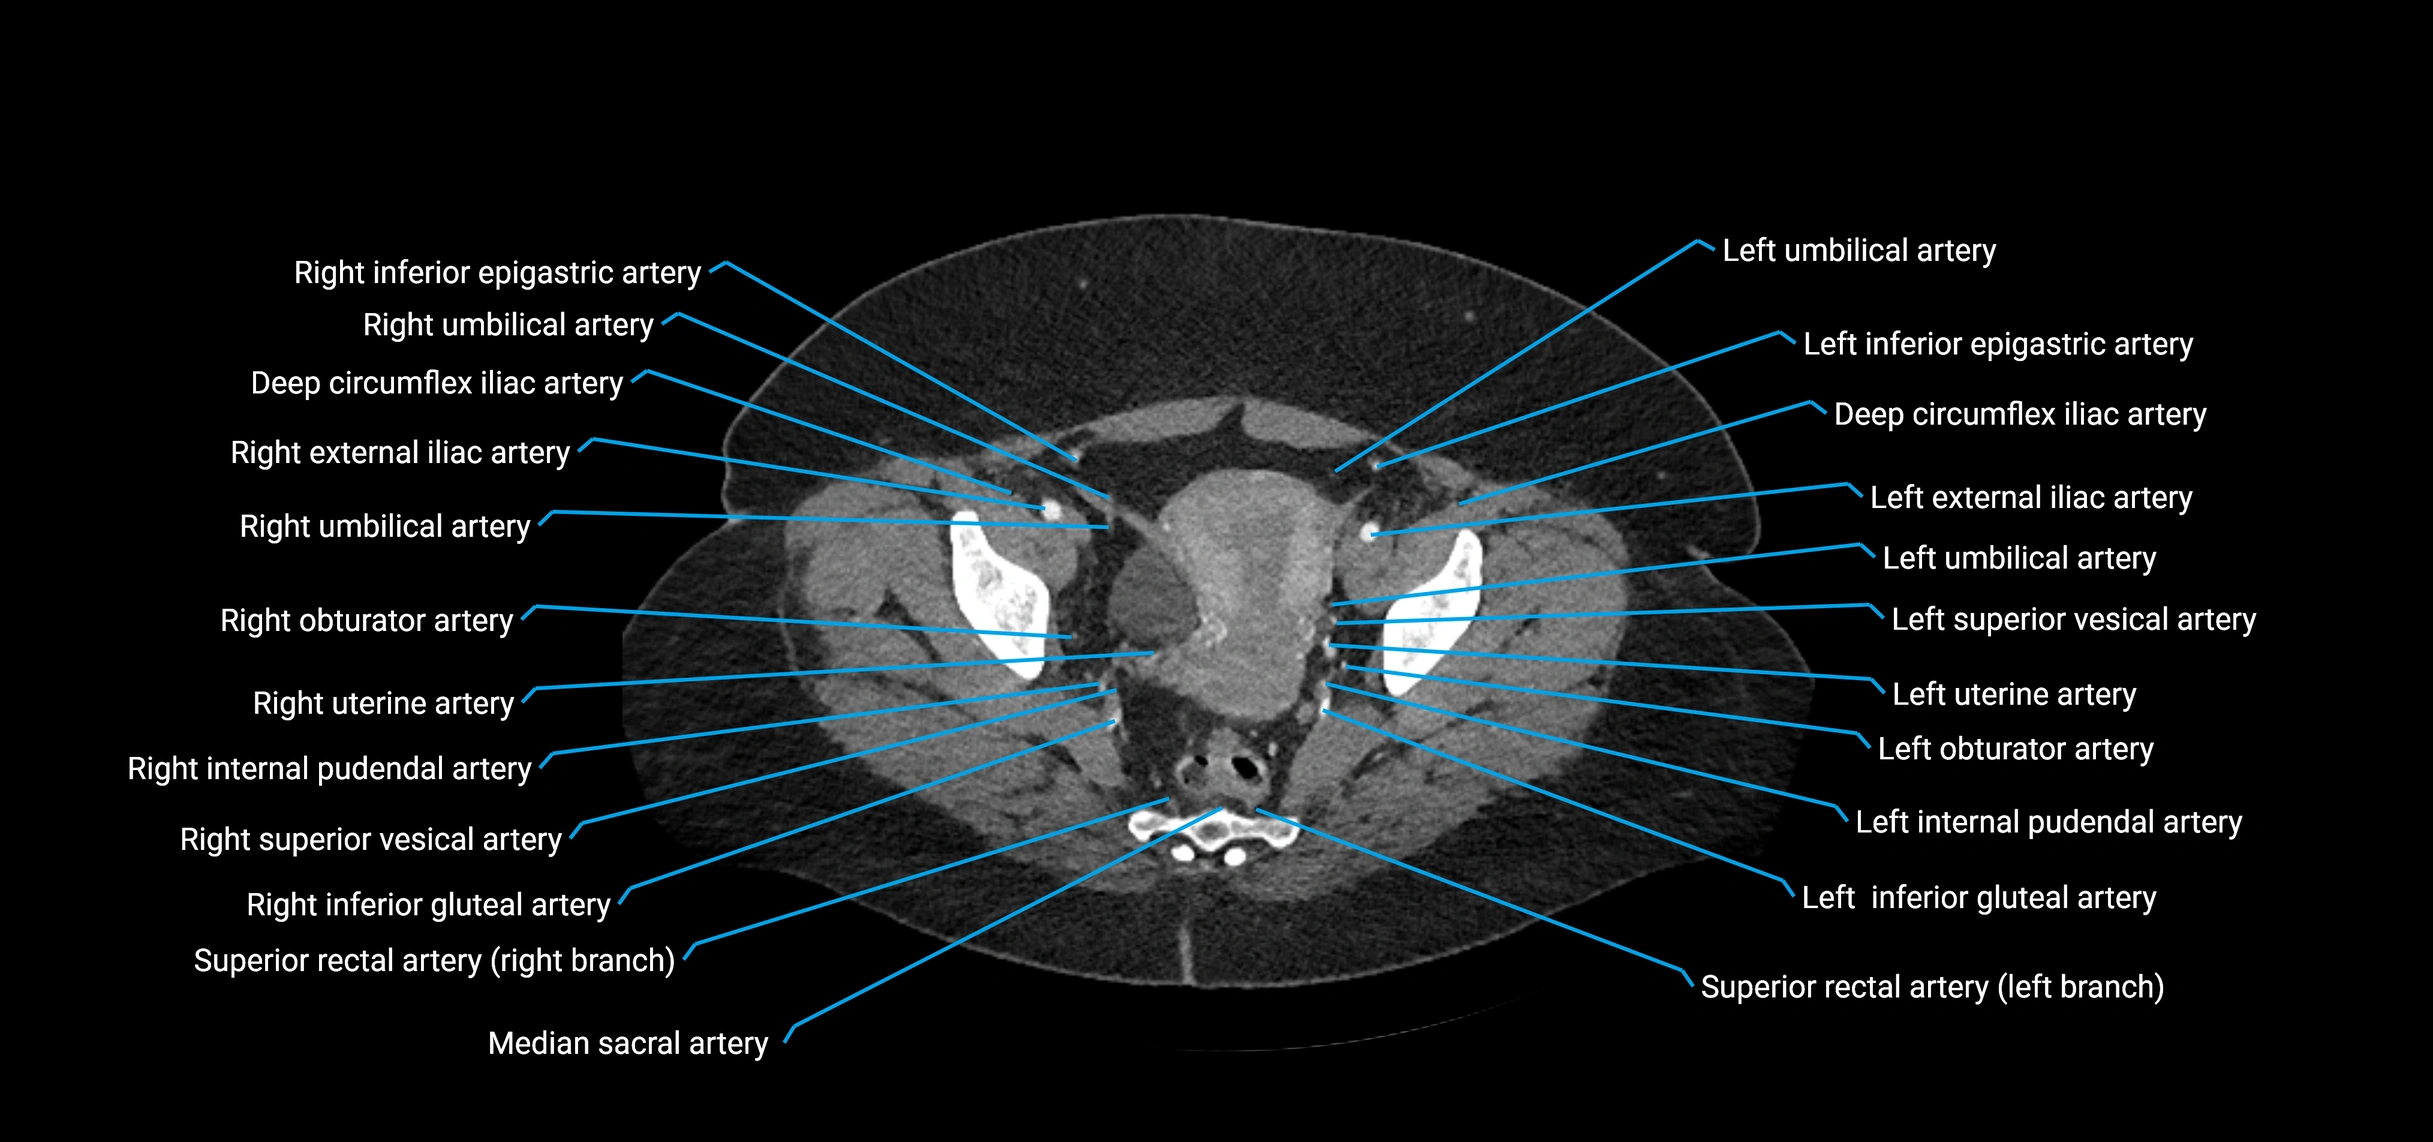

CT Appearance

Non-contrast CT:

• Appears as a tubular soft tissue structure anterior to vertebral bodies

• Calcified atherosclerotic plaques appear as hyperdense foci along the wall

• Useful for screening abdominal aortic aneurysm (AAA) size and mural calcification

Contrast-enhanced CT (CTA):

• Gold standard for abdominal aortic imaging

• Provides excellent detail of lumen, wall, aneurysm, thrombus, and branch vessels

• Multiplanar and 3D reconstructions help in aneurysm measurement, stent graft planning, and dissection evaluation

• Detects acute rupture, traumatic injury, or occlusion with high sensitivity

CT images

image